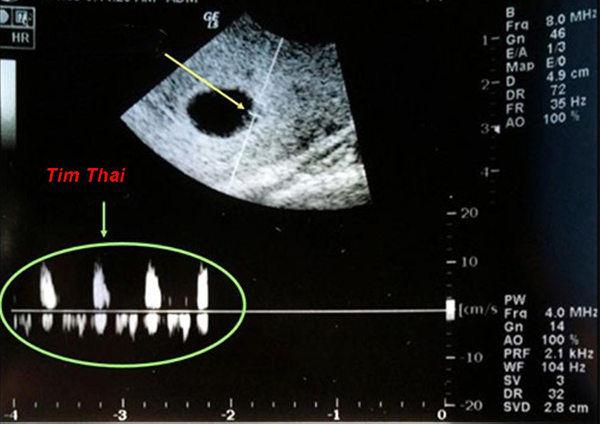

Tuy vậy mẹ vẫn nên theo dõi kỹ. Nếu bị chậm kinh khoảng 2 tuần, bạn nên thực hiện siêu âm để kiểm tra mình có thai hay không, nếu có thì kiểm tra xem thai đã vào tử cung hay chưa. Thông thường, ở cuối tuần thứ 5, đầu tuần 6 thì tim thai chỉ có âm vang. Muốn nghe được nhịp đập của con, mẹ hãy kiên nhẫn đợi sang tuần thứ 7, 8 nhé. Lúc này hình dáng của phôi thai cũng rõ hơn nhiều.

– Real time sonography: có thể kiểm tra và nghe tim thai từ tuần thứ 5.

Thiết bị siêu âm kém chất lượng: Thiết bị siêu âm hoặc ống nghe không đạt chất lượng khiến nhịp tim thai không rõ ràng làm mẹ rất lo lắng, hoang mang. Đặc biệt lúc thai nhi khoảng 6 – 8 tuần tuổi, lúc này tim thai đập yếu nên phải cần một thiết bị đủ nhạy mới có thể nghe được.